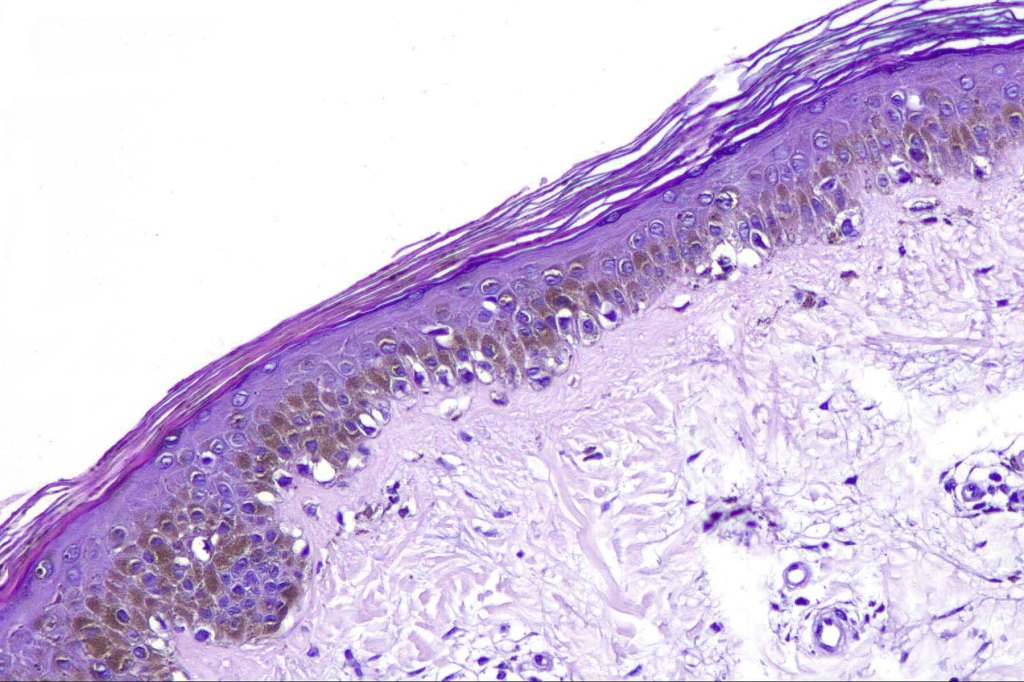

2. Melanocytes generally small, epithelioid (rather than spindled) with either vesicular nuclei and prominent nucleoli or are hyperchromatic.

5. Grey/greenish cytoplasm (due to fine melanin pigment) occasionally encountered

9. SOX10 can be valuable in highlighting the extent of the lesion